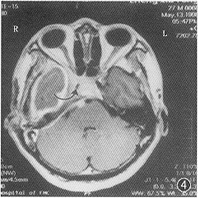

腦梗塞器質性精神障礙是一組由腦部疾病或軀體疾病導致的精神障礙。由腦部疾病導致的精神障礙,包括腦變性疾病、腦血管病、顱內感染、腦外傷、腦瘤等所致精神障礙。軀體疾病導致的精神障礙只是原發軀體疾病症狀的組成部分,也可與感染、中毒性精神障礙統稱為症狀性精神障礙。一般常見類型有:

2、多發腦梗塞性精神障礙。由於腦動脈硬化影響大腦血液供應,特別是反覆發作的腦血管意外所致的痴呆綜合徵。腦外部動脈(頸動脈或錐基底動脈)硬化斑的微栓子或缺血引起大腦白質中心散在性多數小梗塞灶所致,因而稱為多發梗塞性痴呆。本病多在中老年起病,據上海的資料,約占住院的精神病人的1%左右,男性略多於女性。病程多呈階梯式發展,常可伴有局限性神經系統體徵。